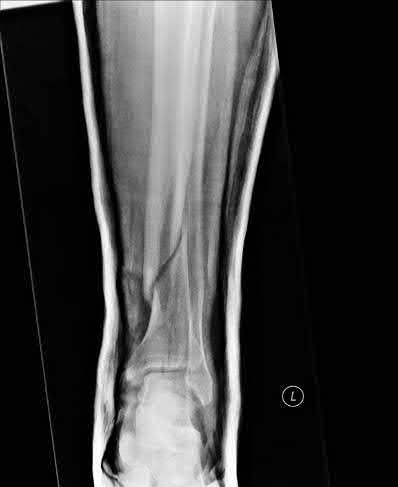

A 25-year-old female is involved in a motor vehicle collision. She presents with the isolated injury seen in Figures A through D. Her leg is swollen but her skin is intact. She has no clinical signs of compartment syndrome. Which of the following treatment options will allow for maintenance of fracture alignment and minimize the risk of soft tissue complications?

The patient presents with a closed distal third metaphyseal-diaphyseal distal tibia fracture with simple intra-articular extension. Immediate intramedullary nailing along with percutaneous fixation of the articular component provides appropriate restoration of length, rotation and alignment and minimizes the risk of wound complication.

Displaced distal third tibia fractures may be associated with simple intraarticular extension. Operative treatment of intra-articular distal tibia fractures has historically been performed with open reduction and internal fixation. Early open reduction and plate fixation of pilon fractures has been associated with high rates of infection and wound complication. In select patterns with simple articular extension, percutaneous screw fixation and medullary nailing may provide appropriate reduction with minimal soft-tissue risk.

Marcus et al. evaluated the outcomes of immediate intramedullary nailing and percutaneous fixation of simple intra-articular distal tibia fractures (AO/OTA 43 C1 and C2). The authors found excellent rates of union and alignment, however caution against broad application of this technique until more rigorous randomized studies can be performed.

Sirkin et al. retrospectively evaluated the results of a staged approach to management of intra-articular distal tibia fractures with temporary bridging external fixation followed by open reduction and internal fixation (ORIF). The authors found decreased rates of wound complication and infection compared with prior studies.

Figures A and B demonstrate a distal third tibial shaft fracture with simple intra-articular extension. The axial and coronal CT cuts in Figures C and D further clarify the articular injury. Illustrations A and B demonstrate a comminuted distal third tibial fracture with simple intra-articular extension. Illustrations C and D are fluoroscopic images of the same injury after intramedullary nailing and percutaneous fixation of the articular component.